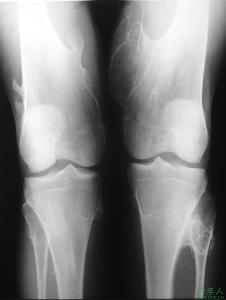

骨软骨瘤严格讲来并不属于肿瘤,而是生长方面的异常,或称错构瘤。瘤体有软骨帽和一个从骨侧面突出的骨组织。骨软内瘤好发于儿童或青年少,一般来说,等到成年后,软骨帽逐渐退化以至消失,偶持久存在并可继发为软骨肉瘤。